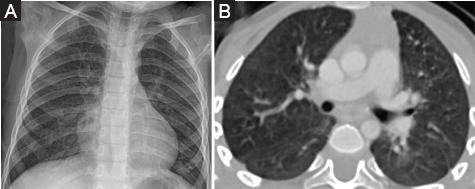

La radiografía de tórax y la tomografía espiral multicorte de tórax mostraron compromiso intersticial difuso bilateral con patrón de vidrio esmerilado (Fig. 1).

Figura 1 A: Radiografía de tórax en la que se observa un patrón intersticial moderado en ambos campos pulmonares. B: Tomografía de tórax en la que se observa compromiso intersticial difuso bilateral moderado con patrón en vidrio esmerilado y pequeñas imágenes quísticas intraparenquimales (1 mes de edad).

En la tomografía se evidenció compromiso pulmonar intersticial con patrón en vidrio esmerilado y algunos quistes pequeños intraparenquimales, similar a lo reportado por Doan, et al.14 en nueve niños con deficiencia en el transportador ABCA3. Debido a que estos hallazgos no son exclusivos de la deficiencia del transportador ABCA3, fue necesario realizar una biopsia pulmonar para su análisis por microscopía óptica y electrónica; esta última para realizar el estudio ultraestructural de los cuerpos lamelares en el interior de los neumocitos de tipo II15.